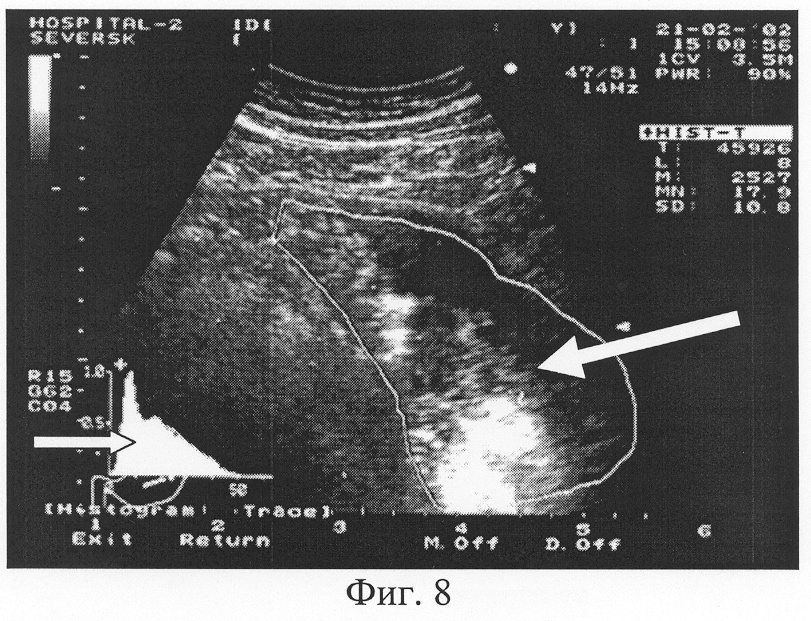

Фиг.8. Трансабдоминальное ультразвуковое исследование желудка. Гистографический анализ содержимого желудка с использованием зоны маркера в виде очерченной ее площади (обозначена стрелкой ). Значение показателя преобладающей эхоинтенсивности MN содержимого желудка составило 17,9 единицы (норматив 6-9 единиц). Графическая кривая гистограммы (обозначена стрелкой ) с несколькими пиками и широким «столиком» графика подтверждает факт неоднородного содержимого желудка, плюс здесь преобладает содержимое повышенной эхоинтенсивности.

Для подсчета коэффициента эхогенности проводится процедура гистографического исследования содержимого желудка, которая аналогична анализу гистограммы содержимого двенадцатиперстной кишки. Технически заключается в построении фронтального либо косого ультразвукового срезов содержимого желудка с целью эхолокации максимально возможного пространства органа. На зафиксированном ультразвуковом изображении выполняется гистография очерченной площади (функция аппаратов ультразвуковой диагностики) содержимого желудка без захвата в зону анализа стенок органа и окружающих тканей (Фиг.7, 8).

Распределение сигналов на графической гистограмме в виде «столика» с несколькими пиками означает неоднородность среды (Фиг.8). Данная картина была обнаружена при исследовании пациентов с признаками нарушения эвакуации содержимого из желудка (остатками фрагментов пищи в желудке) и воспалительными изменениями желудка и двенадцатиперстной кишки.

В результате проведенного исследования нами определен норматив показателя «преобладающей» эхоинтенсивности MN содержимого желудка в выделенном участке изображения, равный 6-9 единицам. В случае превышения этого показателя считаем правомочным определить содержимое желудка как – «эхогенность содержимого желудка повышена», «наличие дополнительной эхогенной взвеси». Эти ультразвуковые параметры будут характерны для задержки эвакуации содержимого из желудка. Данные графической гистограммы в зависимости от количества и остроты пиков будут характеризовать однородность содержимого желудка.